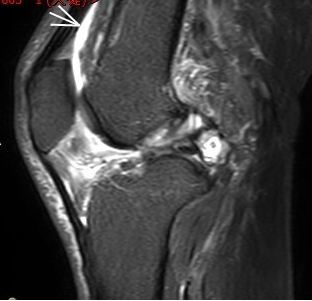

(內(nèi)側(cè)副韌帶損傷)

MRI偵查:揪出前交叉韌帶斷裂(呈“波浪狀”或連續(xù)性中斷)、內(nèi)側(cè)副韌帶損傷,防止關(guān)節(jié)“脫軌”

場(chǎng)景:打球急停后膝蓋不穩(wěn),走路像“踩棉花”